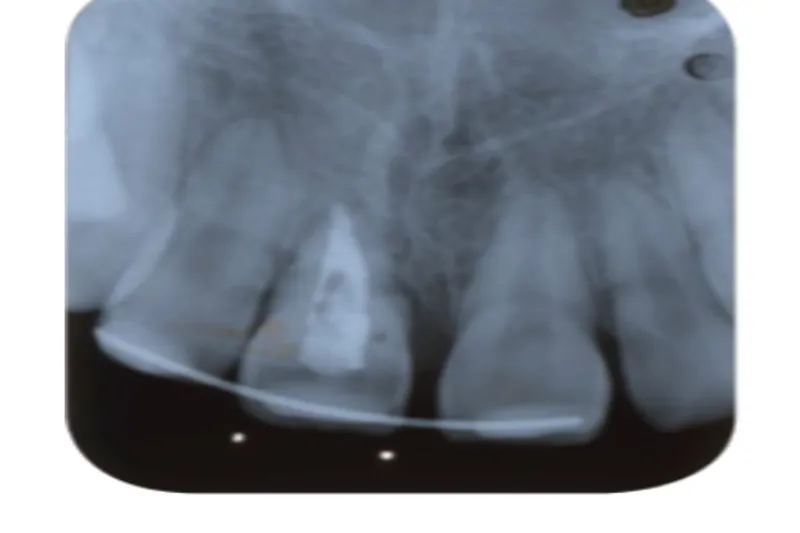

En 10-årig pige eksartikulerede 1+, som blev replanteret på skadestuen efter ca. en time.

Tanden ankyloserede og var tre år efter traumet i ca. 2 mm infraposition.

Der blev foretaget kirurgisk ekstrusion med tang til normal position, og tanden blev fikseret med en elastisk ortodontisk buetråd i to uger.

Efter to år var der pga. fortsat vækst og ankylose igen ca. 2 mm infraposition, men infrapositionen ophørte spontant.